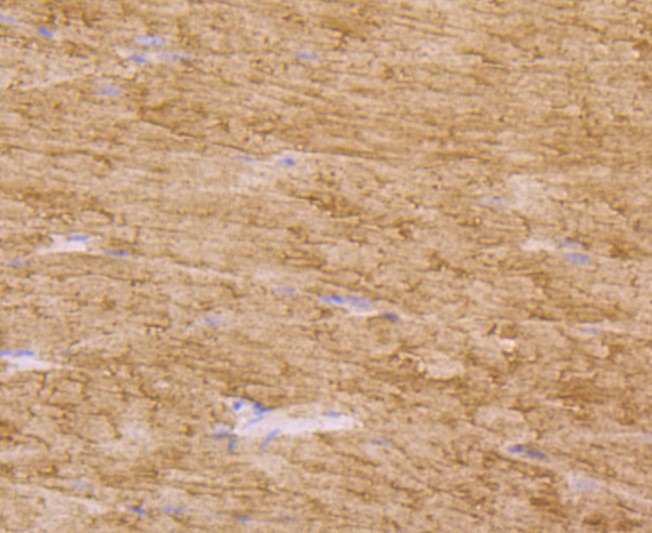

Tissue type plasminogen activator Mouse Monoclonal Antibody [AH54-10]

• IHC-P